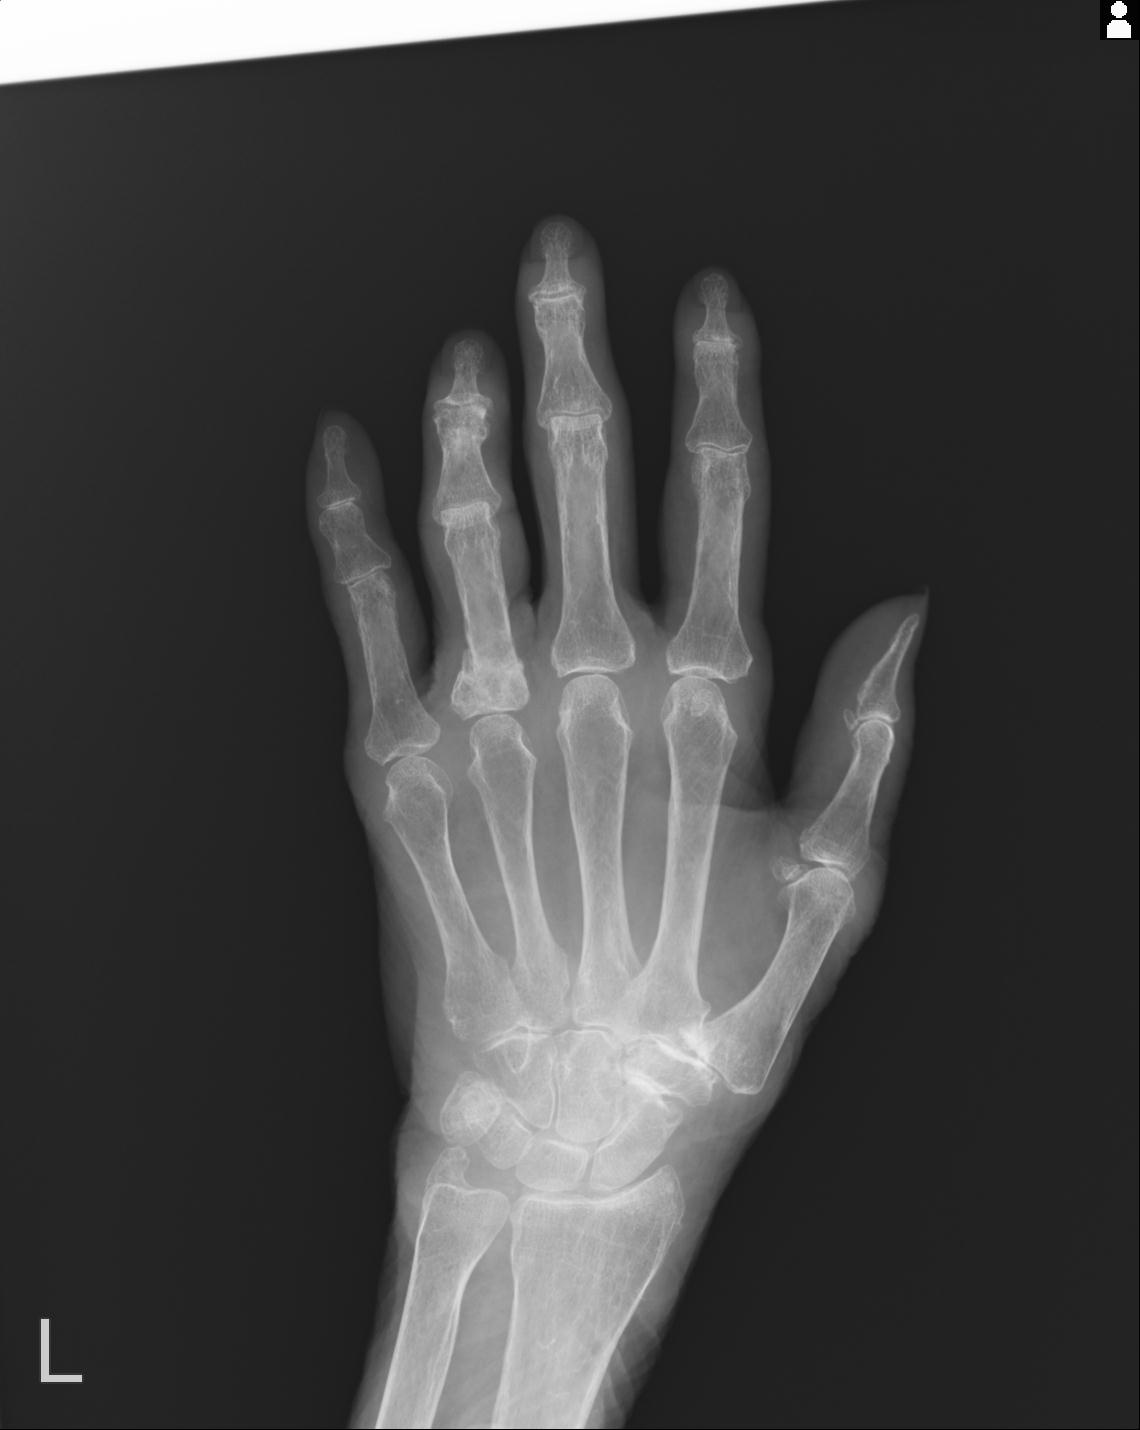

46666 1/23 両股正面+軸と右手関節 2R 76歳女性 右橈骨遠位端

46666 1/28 両股正面+軸と 1/26 右手関節 2R 76歳女性 右転子部骨折

102766 1/5 1/12 左手関節 4R 28歳男性 左橈骨遠位端

50435 1/4 1/15 手関節 4R 17歳女性 右橈骨遠位端

102739 12/30 1/5 左手関節 4R 92歳女性 橈骨遠位端

101290 1/4 5/21 5/20 手関節 2R 17歳男性 橈骨遠位端